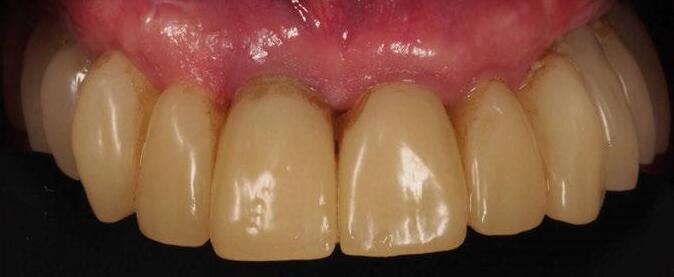

5. Fase protésica definitiva

A los 4 meses, se retiró la prótesis provisional, verificando la